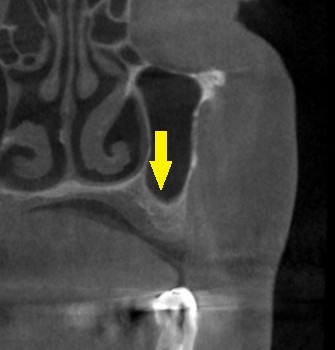

インプラント治療であれば、4歯ないところへ、2本のインプラントを埋入して、3歯回復を目指したいのですが、CTで見ると、特に2本目のインプラントを埋入したいところは、骨が非常に薄い状態でした(下の写真上段右)。

ワイドインプラントでも対応が困難と考え、サイナスリフトという骨造成をまず行って、骨量を確保することを提案させていただきました。

ご了承いただけましたので、本日、左側上顎のサイナスリフトを施行しました。

下の写真下段が手術後のCTです。